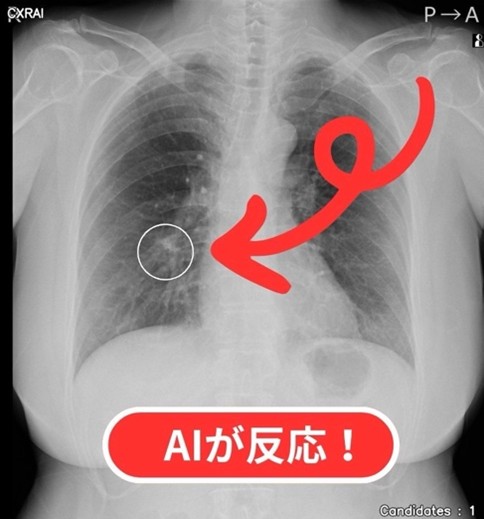

胸のレントゲンにAIを導入しました!

当院では、胸部レントゲンをもっと正確に読むために、AI(人工知能)のサポートシステム 「CXR Finding-i」 (コニカミノルタ社製)を導入しました!

レントゲン写真には、肺が心臓や骨などに重なって「見えにくい場所」があります。

医師も注意して見ていますが、それでも小さな影を見逃してしまう可能性はゼロではありません。

AIは、専門医が学んできた読影(レントゲンを見る技術)を学習していて、肺がんのもとになる「しこり」や、肺炎・結核などで出てくる「影」を自動で見つけてマークしてくれます!

実際に、AIが「ここが怪しいですよ」と教えてくれた部分をCTで詳しく調べたら、肺炎が見つかったこともありました!